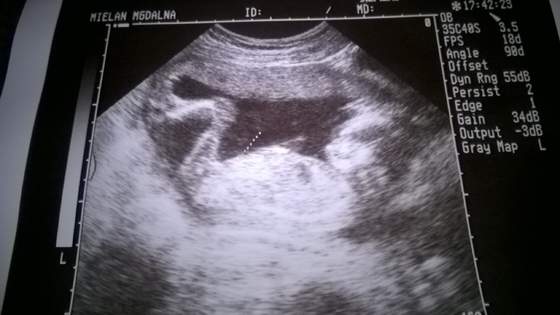

Zobacz załącznik 723053. Nasza córciamierzy okolo 16 cm ima się dobrze

na tym zdjęciu widac ze leży normalnie a tak naprawdę leży główka na dol